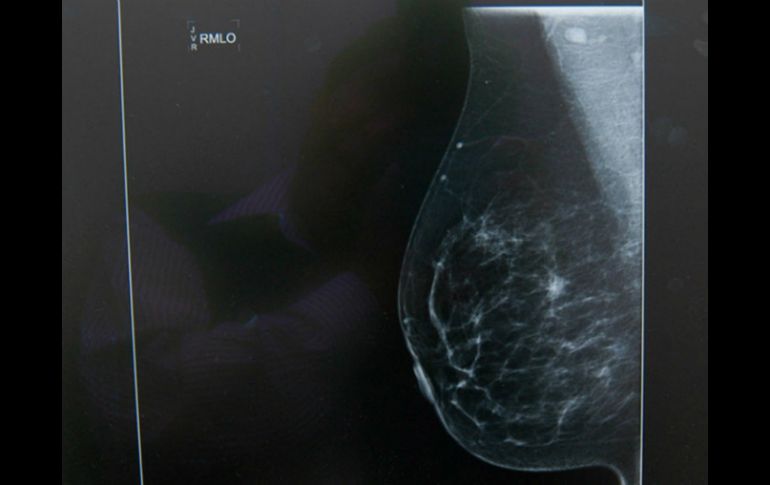

Tecnología | 'Thermy'usará inteligencia artificial para registrar el calor de la piel con una cámara Jóvenes mexicanos desarrollan 'app' para detectar cáncer de mama 'Thermy' usará inteligencia artificial para registrar el calor de la piel con una cámara termográfica Por: NTX 22 de octubre de 2015 - 18:04 hs La cámara debe detectar por medio de la temperatura cuando las células cancerígenas se multiplican y crecen. NTX / ARCHIVO CIUDAD DE MÉXICO (22/OCT/2015).- Un grupo de jóvenes mexicanos trabaja en el desarrollo de una aplicación para dispositivos móviles como celulares, tabletas y computadoras, que analizará las imágenes termográficas y los datos clínicos para detectar el cáncer de mama. La aplicación denominada Thermy consistirá en un software conformado por datos clínicos y estadísticos con el uso de inteligencia artificial, la cual se complementará con una cámara termográfica que registrará el calor de la piel. La implementación de este tipo de cámara se debe a que cuando las células cancerígenas se multiplican y crecen, el flujo sanguíneo y el metabolismo aumentan, lo que provoca un incremento en la temperatura de la piel. En una entrevista para la Agencia Informativa del Conacyt, el líder del proyecto, Ricardo Niño de Rivera, detalló que trabajan en la creación del algoritmo a partir de la base de datos sobre el cáncer de mama de la Universidad Federal Fluminense de Brasil. Una vez que comprueben que tiene una sensibilidad superior al 80 por ciento, el equipo de investigación conformará su propia base de datos con la toma de alrededor de 200 muestras de pacientes mexicanas para comprobar su efectividad en la población de México. "Estamos usando biodatos y datos de la termografía, se analiza la diferencia entre una mama y la otra para detectar si hay cáncer. Con las muestras que recabemos se podrá tener una buena fuente de información para saber qué datos son más significativos", indicó Niño de Rivera. Si bien, Thermy será una alternativa de detección oportuna porque analizará imágenes termográficas y datos clínicos mediante las técnicas de visión e inteligencia artificial, el ingeniero aclaró que no suple a la mastografía ni la vigilancia médica. Además de Niño de Rivera, en el proyecto participan el también egresado del Instituto Politécnico Nacional (IPN), César Ernesto López, ingeniero en Mecatrónica. Así como el egresado del Instituto Tecnológico de Monterrey, Aldo Estefano Encarnación, así como Mario Ortega, Pedro Abraham Sánchez, Miguel Garrido y Héctor Moncada. En su oportunidad, Encarnación destacó que esta aplicación se podría usar en las zonas donde no se tiene acceso fácil a los mastógrafos. "La idea es mantenerlo lo más simple posible, que un médico pueda tomar la cámara, su dispositivo móvil (en caso de que sea una aplicación móvil) o su computadora portátil (si es una aplicación web) y llevar su portafolio a algún pueblo que no cuente con servicios médicos", dijo el ingeniero en biotecnología. Los desarrolladores pretenden que el médico se instale en una habitación y tome las imágenes de la paciente, las analice y en ese mismo momento pueda decir si existen indicios de cáncer y recomendar la realización de una mastografía. Los creadores de Thermy trabajan para que en el menor tiempo posible la aplicación funcione para el beneficio de las mexicanas. De acuerdo con datos del Instituto Nacional de Estadística y Geografía ( INEGI), de cada 100 mastografías en 2013, se hicieron 30 en el Distrito Federal, siete en Baja California y seis en Jalisco. Mientras que en seis estados el porcentaje de mastografías no alcanza el uno por ciento, siendo el caso más extremo Quintana Roo, con 0.5 por ciento. El año con mayor incidencia de cáncer de mama en las mexicanas fue 2014, al registrarse 28.75 casos nuevos por cada 100 mil mujeres de 20 años o más, una tendencia que va en aumento y que se aceleró desde 2007 a la fecha, de acuerdo con datos del INEGI. Temas Ciencia médica Cáncer de mama Calor de hogar Aplicaciones Lee También Así influye la Luna en el movimiento de las olas del mar, según científicos Guadalajara amanece fresco, pero viene calor por la tarde FOX One: La nueva plataforma que transmitirá la Liga MX y otras competencias Sheinbaum presenta un nuevo modelo de atención universal al cáncer de mama Recibe las últimas noticias en tu e-mail Todo lo que necesitas saber para comenzar tu día Registrarse implica aceptar los Términos y Condiciones